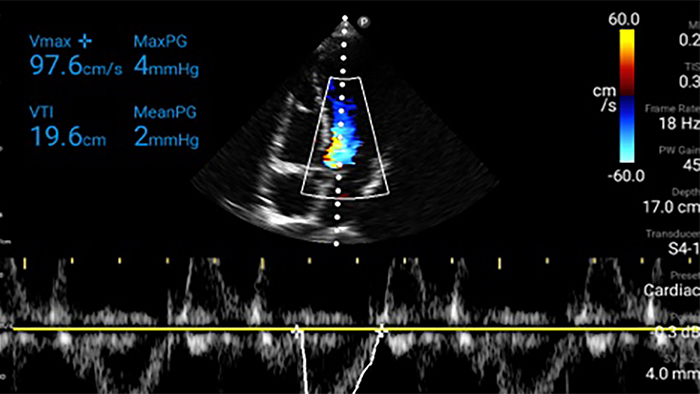

Congestive heart failure is a growing issue today. Discovering it earlier with in-office ultrasound can greatly improve survival rates.

Assessment of left ventricular function